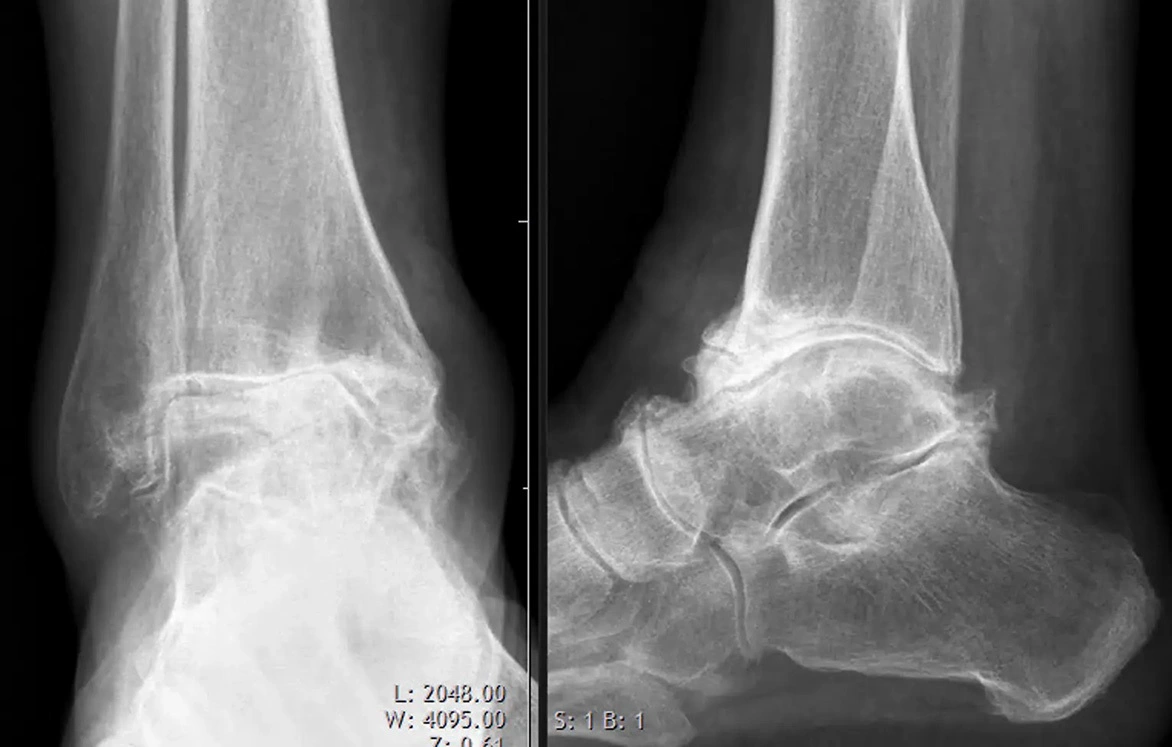

Röntgenbild eines Fusses

Die Diagnose einer OSG-Arthrose erfolgt in der Regel durch eine Kombination aus körperlicher Untersuchung und Bildgebung. Zunächst reicht oft ein Röntgenbild, um die Diagnose zu bestätigen und mögliche Risikofaktoren, z.B. Fehlstellungen, zu identifizieren. Je nach Verlauf und je nach notwendiger Therapie können weitere diagnostische Massnahmen (MRI oder CT) notwendig werden.